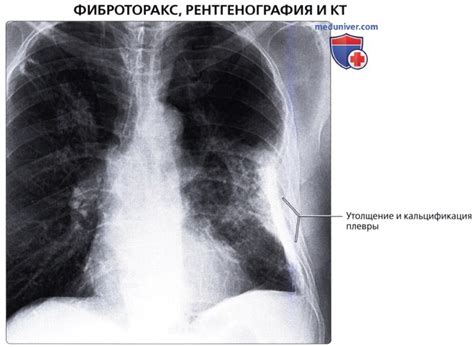

Утолщение костальной плевры может сопровождаться различными симптомами, такими как боль в груди, затрудненное дыхание, кашель, ощущение сдавленности. Однако утолщение костальной плевры часто является следствием основного заболевания и может быть обнаружено только при проведении дополнительных исследований, таких как рентген грудной клетки или компьютерная томография.

| Рентгенография грудной клетки | Рентгенологическое исследование позволяет получить изображение грудной клетки, чтобы выявить изменения в легочной и плевральной области. Оно может помочь определить утолщение костальной плевры и обнаружить другие патологии. |

| Компьютерная томография | Использование компьютерной томографии позволяет получить 3D-изображение грудной клетки и обнаружить патологические изменения, включая утолщение костальной плевры. Этот метод часто применяется в случаях, когда другие методы исследования не позволяют однозначно диагностировать состояние плевры. |